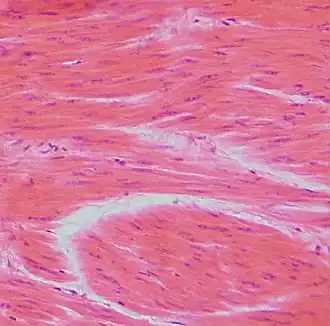

Клетки гладкой мускулатуры

Гладкомышечные клетки называются так, потому что у них нет ни миофибрилл, ни саркомеров, и, следовательно, нет «полос». Они обнаруживаются в стенках полых органов, включая желудок, кишечник, мочевой пузырь и матку, в стенках кровеносных сосудов, а также в путях дыхательной, мочевыделительной и репродуктивной систем. В глазах цилиарная мышца расширяется и изменяет форму хрусталика. В коже гладкомышечные клетки волосяного фолликула заставляют волосы встать дыбом в ответ на холод или страх.[3]

Гладкомышечные клетки имеют веретенообразную форму с широкими серединами и сужающимися концами. Они имеют одно ядро и имеют длину от 30 до 200 микрометров. Это многократно короче волокон скелетных мышц. Диаметр также намного меньше, что устраняет необходимость в Т-канальцах, обнаруженных в поперечно-полосатых мышечных клетках. Хотя в гладкомышечных клетках отсутствуют саркомеры и миофибриллы, они содержат большое количество сократительных белков актина и миозина. Нити актина прикреплены плотными телами (подобными Z-дискам в саркомерах) к сарколемме.[3]